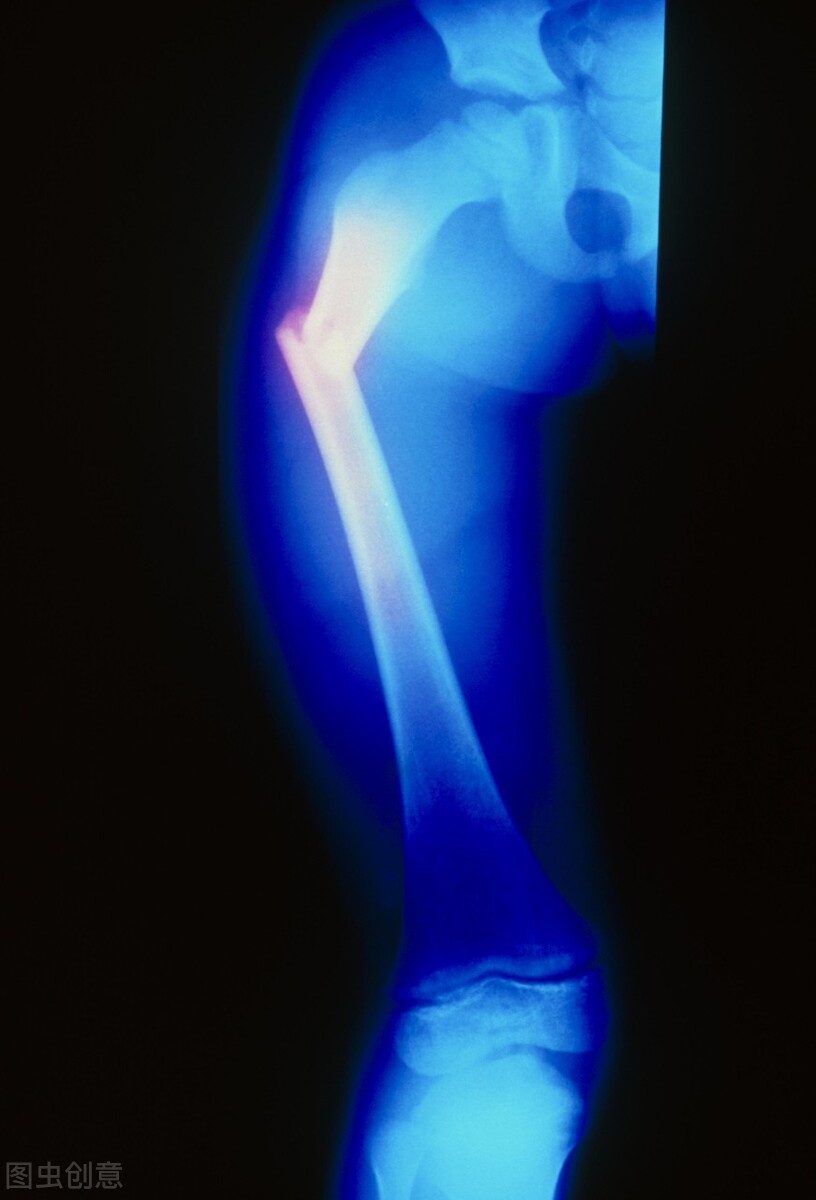

孩子的大腿骨折处,在术后第三天,就出现了肿胀畸形,医生们心里都清楚,股骨干骨折端两侧的大腿肌肉,产生了强大的剪力,又一次,把骨折拉移位了,钢板螺钉肯定全松掉了。

老主任只能说孩子体质特殊,骨头松,固定的螺钉拉不住,现在骨折又移位了,床边拍片也应证了这一个不好的结果。

老主任仔细研究了X片,发现固定骨折的钢板螺钉没有全部松动,还是有几枚螺钉有一定拉力的。

骨折对位移位,对线有了成角畸形了,再次手术的话,孩子又要遭受一次创伤,老主任想,还是用治疗儿童骨折的老办法吧。